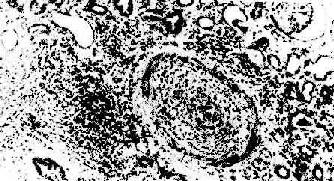

图4-5 肾移植急性排斥反应

小叶间动脉呈纤维素样坏死,并有大单核细胞及中性白细胞浸润和血栓形成